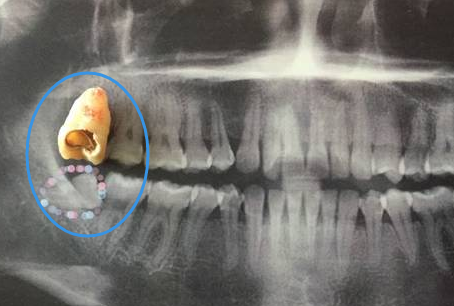

通常情況下,隻要自身發現有智齒後,都建議大家可以到專(zhuan) 業(ye) 的口腔醫院的拍片查看智齒的情況,因為(wei) 智齒有的可以看到牙冠,有的看不到牙冠,牙根深埋在牙槽骨內(nei) ,各種妖嬈的姿勢都有,特別是牙根,所以相對來說,是很複雜的,因此拔還是不拔,需要看牙片才能決(jue) 定。

從(cong) 牙片上看,如果是智齒位置很正,而且上下都有,或者是能夠正常萌出的,沒有發炎過,也沒有造成鄰牙齲壞的,可以想觀察一下,先不用拔牙。但是這種占少數,目前大部分的智齒位置都是歪著的,方向亂(luan) 七八糟的,不僅(jin) 會(hui) 齲壞鄰牙,甚至造成牙齒擁擠,智齒經常發炎疼痛等。

所以如果發現智齒位置不正,即便是現在不痛不腫不難受,也可以提前拔除,不一定非要等到危害產(chan) 生後再進行拔除,還有一個(ge) 辦法,如果是實在不想拔除智齒的,而且有正畸打算的,可以先到正畸科檢查一下,是否可以把智齒利用起來,這樣就不需要拔除智齒了。